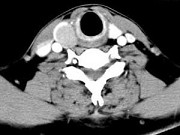

男,43岁,右颈部扪及一包块,CT如图所示,应诊断为()

A.甲状腺腺瘤

B.甲状腺腺癌

C.结节性甲状腺肿

D.甲状腺原发淋巴瘤

E.甲状腺转移瘤

男,43岁,右颈部扪及一包块,CT如图所示,应诊断为()。

[单选题,A2型题,A1/A2型题] 男,43岁,右颈部扪及一包块,CT如图所示,应诊断为()。A . 甲状腺腺瘤B . 甲状腺腺癌C . 结节性甲状腺肿D . 甲状腺原发淋巴瘤E . 甲状腺转移癌

男,43岁,右颈部扪及一包块,CT如图所示,应诊断为()

[单选题]男,43岁,右颈部扪及一包块,CT如图所示,应诊断为()A .甲状腺腺瘤B .甲状腺腺癌C .结节性甲状腺肿D .甲状腺原发淋巴瘤E .甲状腺转移瘤

男,43岁,右颈部扪及一包块,CT如图所示,应诊断为()

[单选题]男,43岁,右颈部扪及一包块,CT如图所示,应诊断为()A . 甲状腺腺瘤B . 甲状腺腺癌C . 结节性甲状腺肿D . 甲状腺原发淋巴瘤E . 甲状腺转移癌